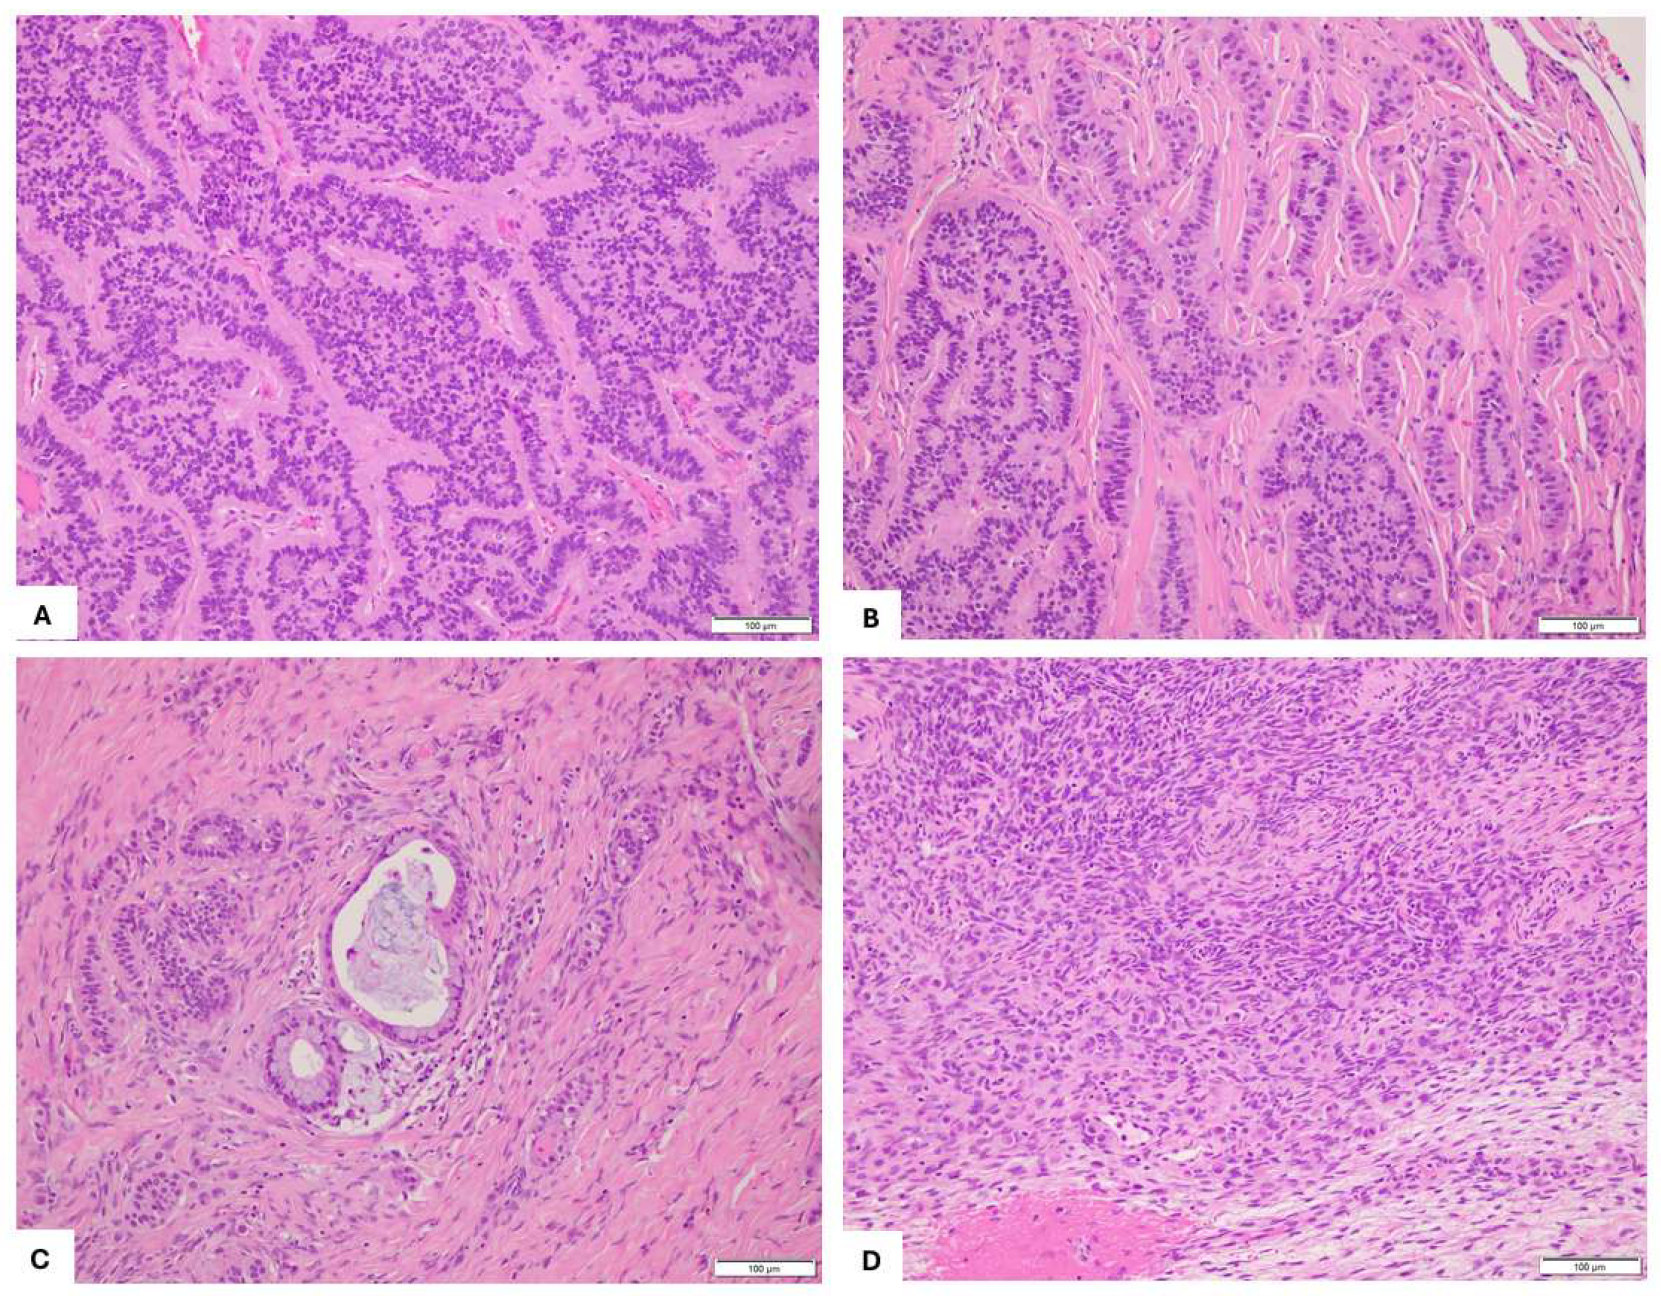

2. Case Presentation